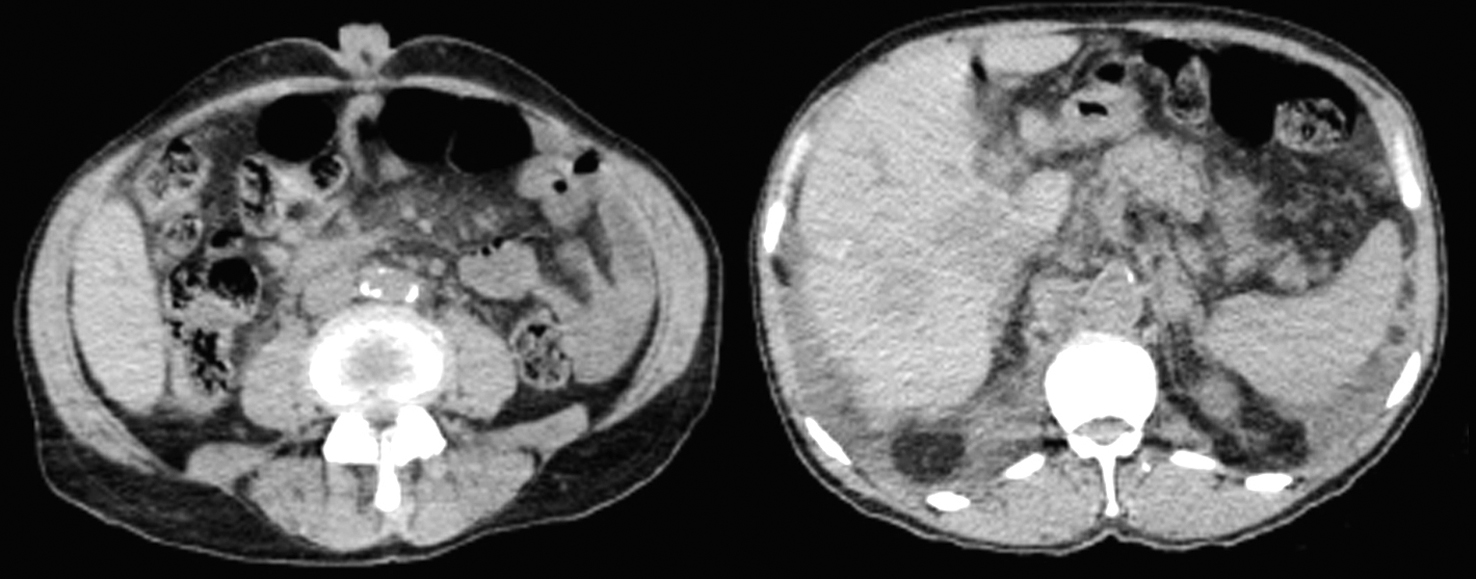

Figure 2 - Simple computed tomography revealing abundant intraabdominal lymph node chains and an umbilical nodule (a, b)

The CT scan revealed atypical lymphatic activity at abdominal, retroperitoneal, supraclavicular, mediastinal, mesenteric, peripancreatic level which is associated to hepatic density changes of infiltrative appearance, considered secondary to neoplastic activity. Presence of nonspecific morphologic changes of the pancreatic head with the possibility of primary activity being at this level. Bilateral pleural effusion of a 40% and pericardial effusion. Centrilobular emphysema type COPD, cholelithiasis, bilateral renal hypertrophy data but there is no mention of the umbilical nodule.